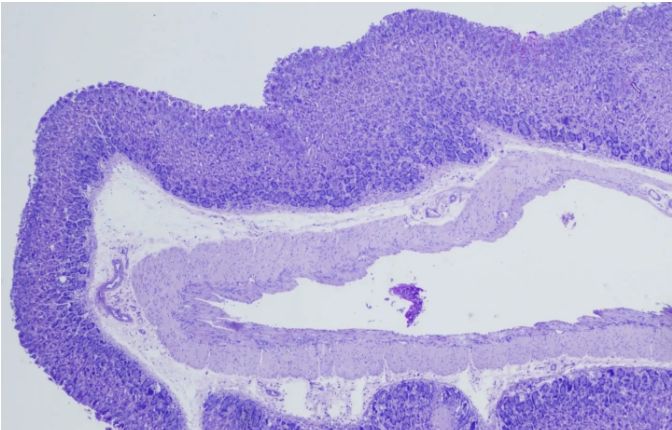

[圖1]

首先,我們需要了解PAS染色的基本原理——過(guò)碘酸能夠氧化組織中的多糖類(lèi)物質(zhì),使其形成醛基或酮基。隨后,雪夫試劑與這些醛基或酮基發(fā)生反應(yīng),生成不溶于水的有色化合物,從而在顯微鏡下呈現(xiàn)出特定的顏色。這種顏色反應(yīng)不僅具有高度的特異性,而且敏感性也很高,能夠準(zhǔn)確反映組織中多糖類(lèi)物質(zhì)的分布和含量。

一、染色強(qiáng)度和分布

染色強(qiáng)度的深淺可以反映組織中多糖類(lèi)物質(zhì)的含量。一般來(lái)說(shuō),染色越深,說(shuō)明多糖類(lèi)物質(zhì)含量越高;反之,染色越淺,則含量越低。同時(shí),我們還需觀察染色的分布情況,以了解多糖類(lèi)物質(zhì)在組織中的具體位置和形態(tài)。